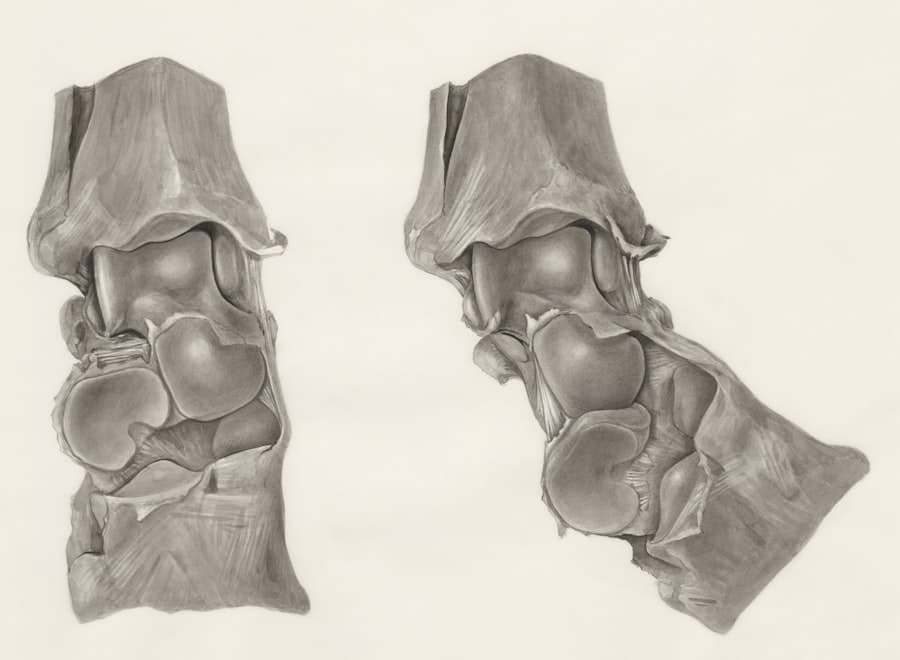

For a procedure that impacts both the form and function of your nose, board certification provides a vital layer of assurance. Rhinoplasty requires a deep understanding of facial anatomy, aesthetic principles, and the delicate balance between cosmetic enhancement and maintaining nasal respiration.

The nose is not just a facial feature; it is a vital organ for breathing. A surgeon must have a thorough understanding of nasal anatomy and physiology to ensure that any surgical modifications do not compromise airflow.